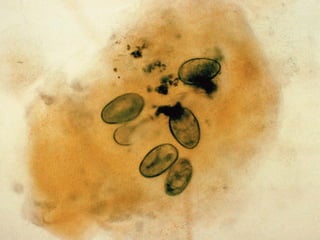

The document references a verse from the Quran (Al-A'raf: 133) discussing the plagues sent as signs to a people who were arrogant and sinful. It mentions various afflictions such as locusts, blood, frogs, and lice. The context highlights the consequences faced by those who rejected the divine signs.